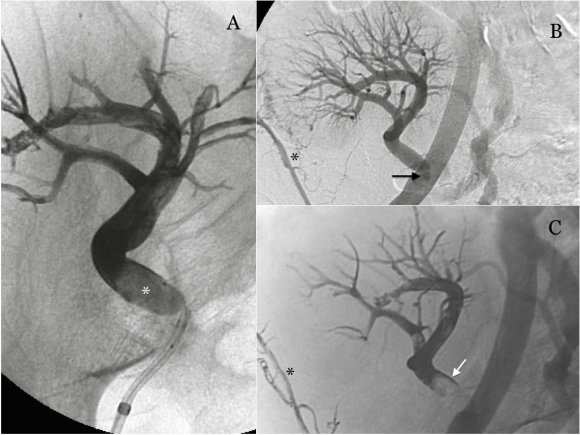

From 2009 to 2014 31 cases were obtained with the inclusion criteria mentioned, of whom 54.8 % were women and 45.2 % were men with a median age of 57 years (range 36 to 84 years); all with a study of abdominal computed tomography. The organs affected by GIST were 51.6 % (16) stomach, 22.6 % (7) jejunum, 12.9 % (4) rectum, 6.5 % (2) duodenum, 3.2 % (1) peritoneum and 3.2 % (1) retroperitoneum (Table 2). 32.3 % (10) of the patients were surgically treated before starting with Imatinib. 67.7 % received first-line molecular targeted therapy with Imatinib, and 32.3 % received second line with Sunitinib. We assessed the response to treatment with a CT scan in an average of 1 to 24 months. According to the criteria of CHOI, we observed 45.2 % (14) complete response, 19.4 (5) stable disease, 19.4 (6) partial response and 16.1 % (5) disease progression (Table 3) Figures 1,2, 3. During that time, metastatic activity was observed in 14 patients representing a 45.1 %, with predominant involvement in the liver with a percentage of 35.5 % of the total (Table 4) Figure 4.